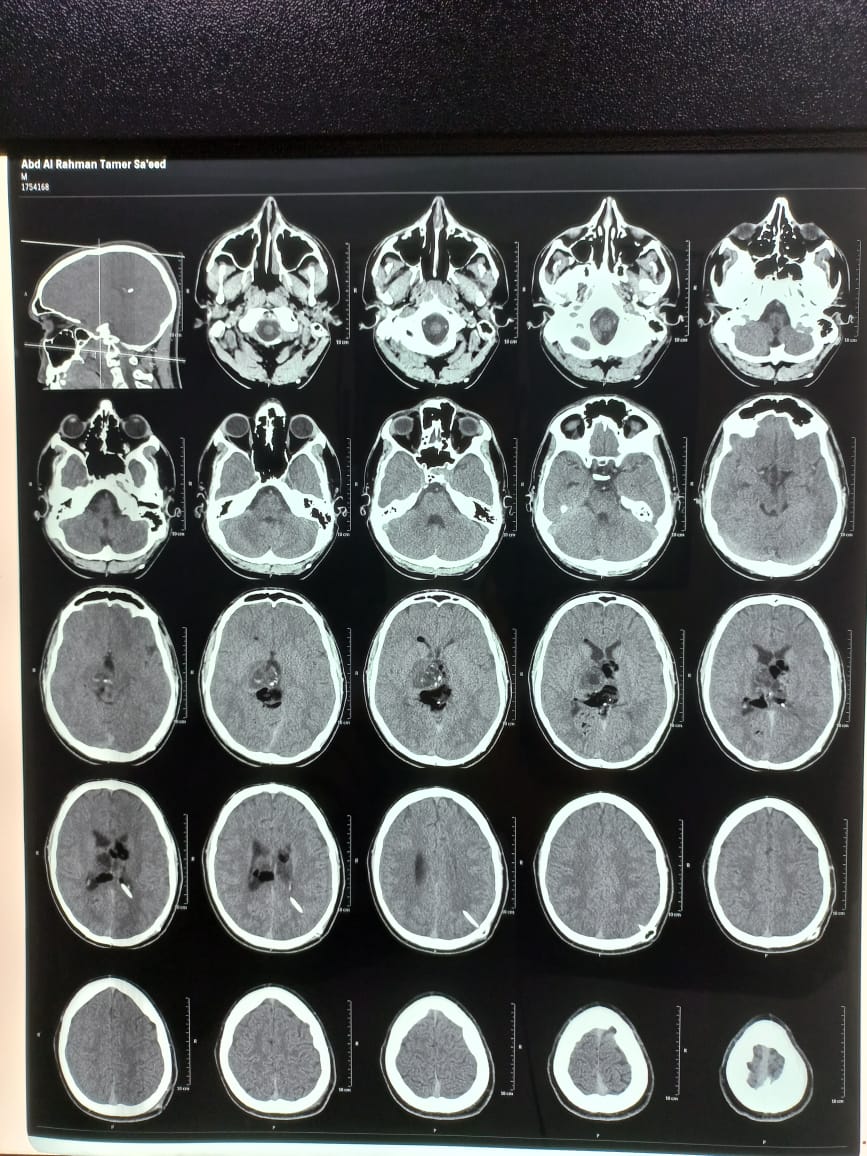

تعرض عبد الرحمن تامر، مواليد 2004، لاعب فريق كرة اليد بنادي الطيران، لمرض شديد الفترة الأخيرة، حيث إنه يعاني من 2 ورم فى المخ بأماكن خطرة.

وكشف الأطباء المعالجين له، أن الورم الأول عمل ارتشاح فى المخ وأثر على عينه تسبب فى حول، وأجريت عملية سريعة لإنقاذ حالته وتم نزع الورم المسبب للارتشاح وعمل صمام بالمخ نازل على المعدة لصرف الارتشاح.

فيما جاء الورم الآخر كبير فى مكان حساس فى المخ وحجمه يكبر وتسبب فى عوج للفم ويتطلب لإجراء عملية سريعة، وناشد اللاعب المسؤولين لمساعدته في العلاج ومواجهة المرض.